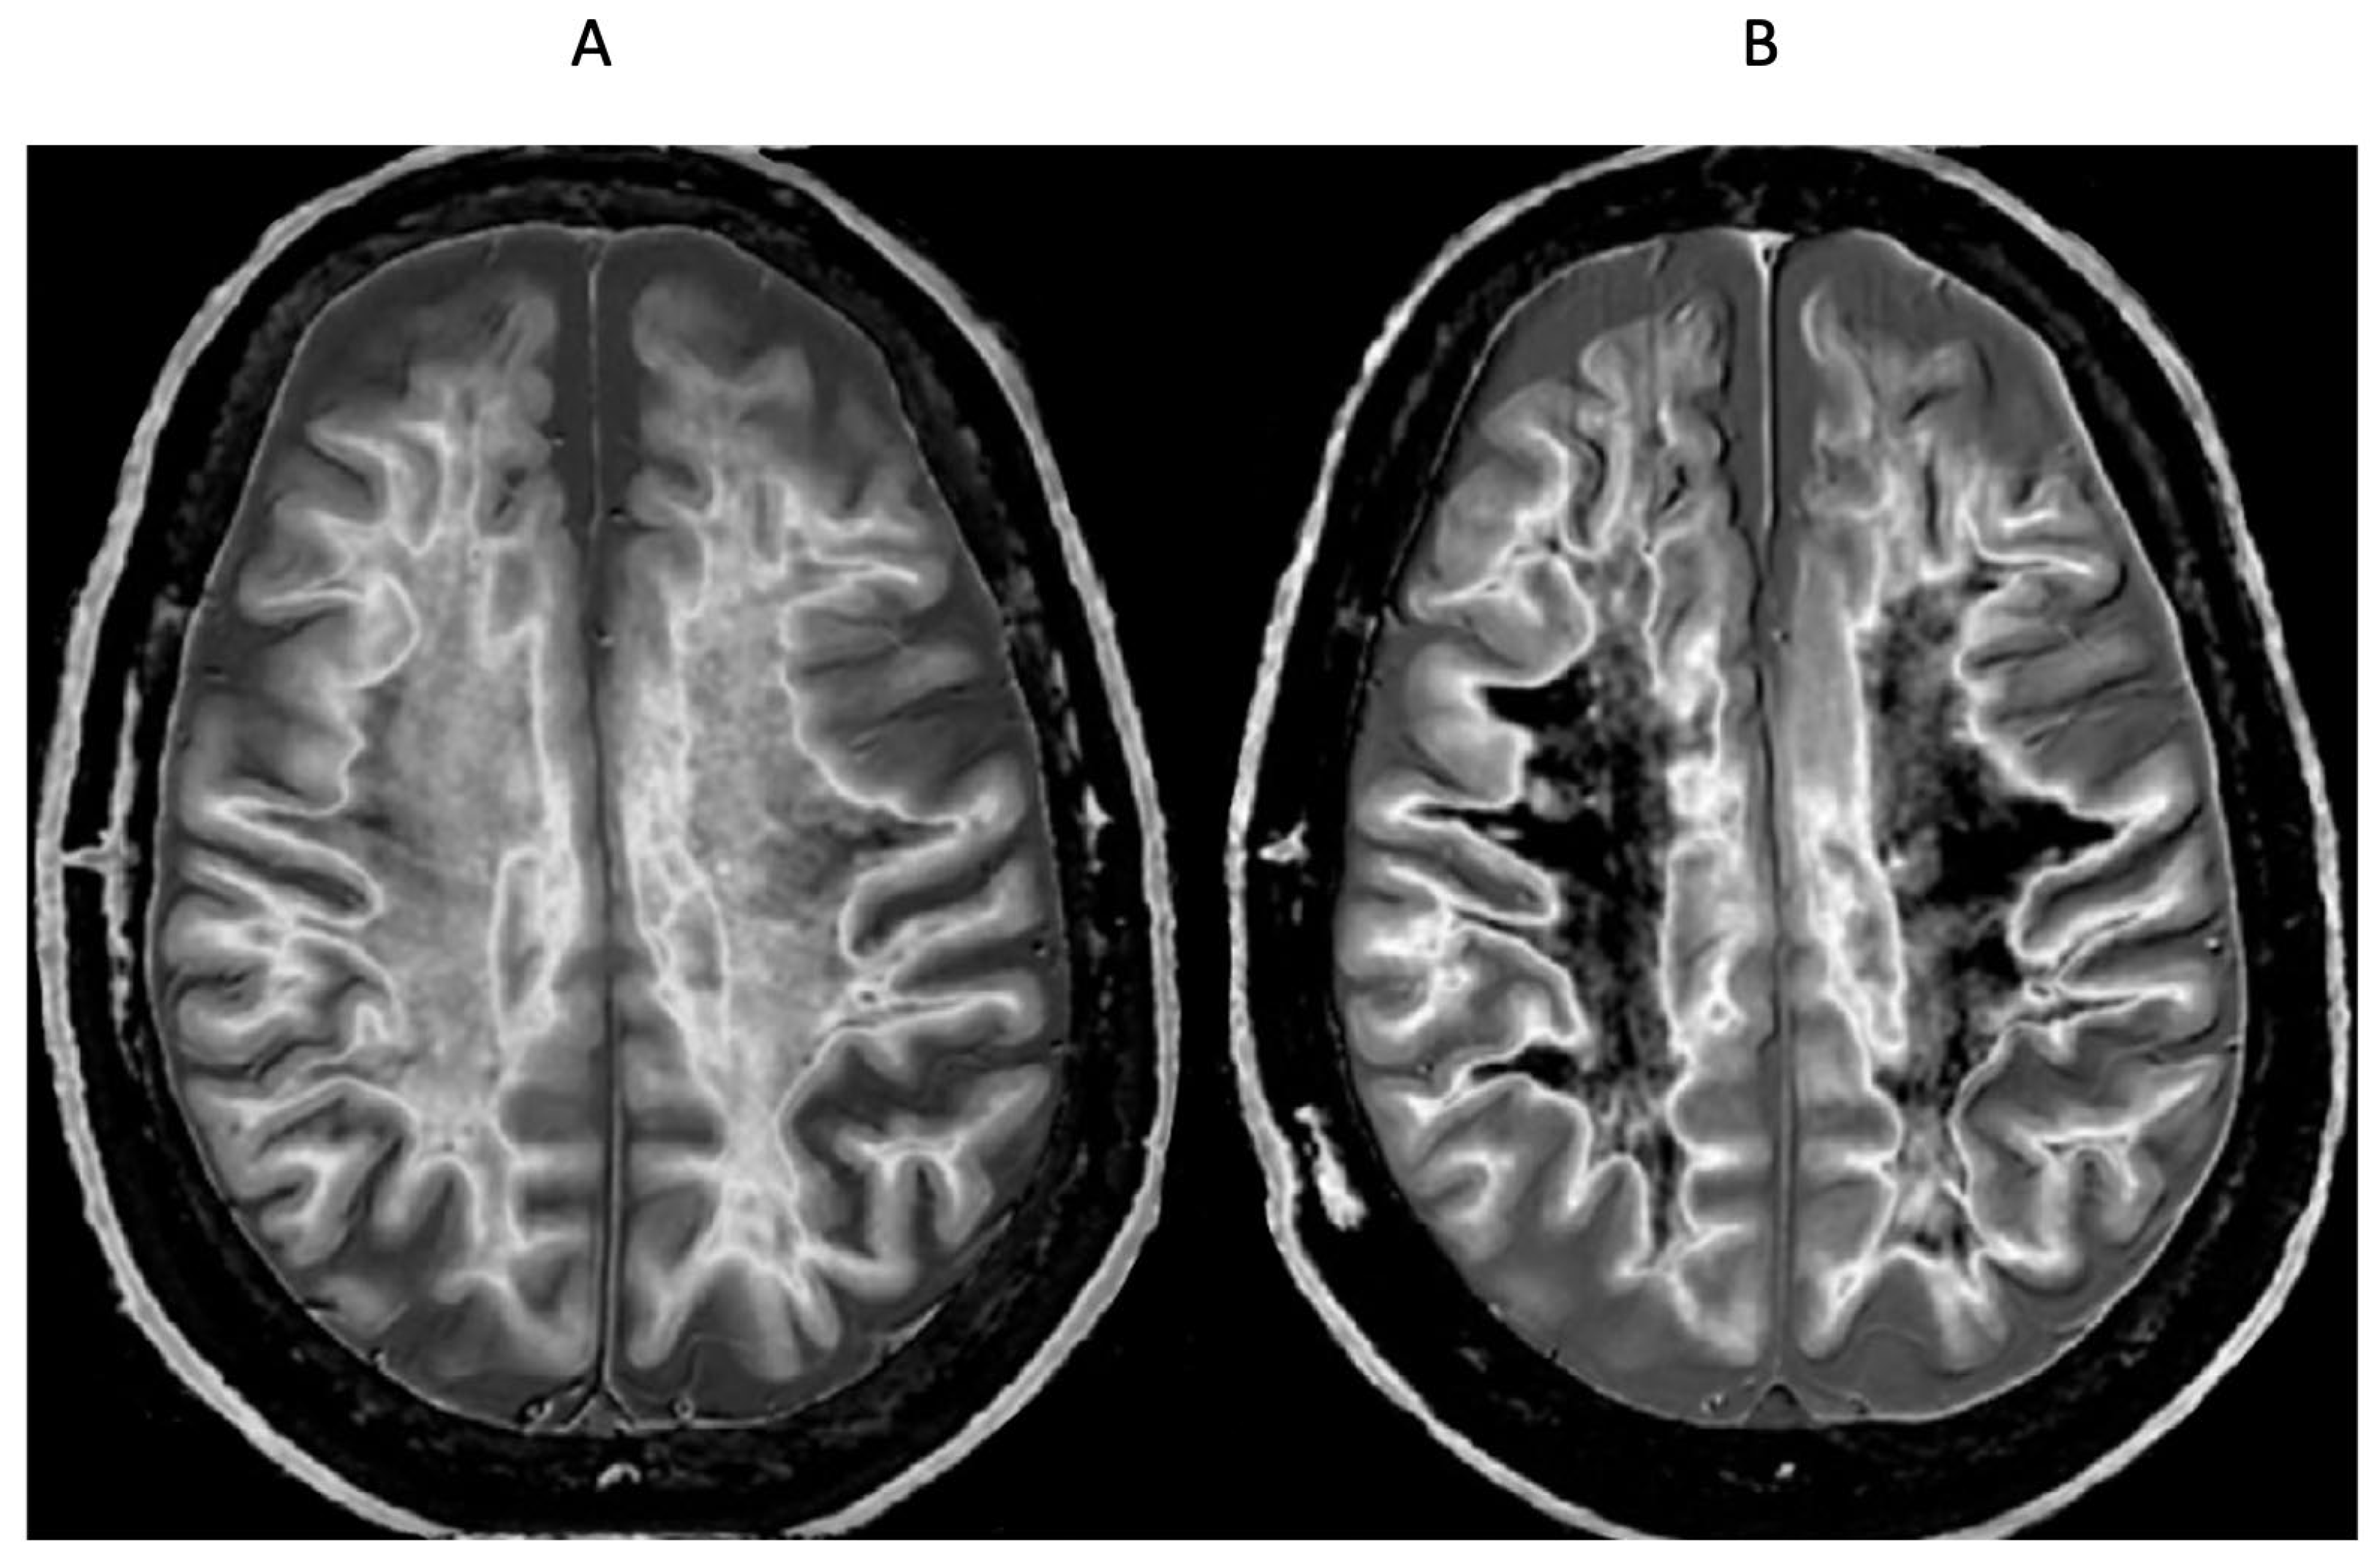

Figure 19.

51-year-old male patient with methamphetamine substance use disorder after one month’s abstinence (A) and after nine months’ abstinence (B). Matched narrow mD dSIR images. In (A) there is extensive high signal in the white matter of the cerebral hemispheres with only small areas of normal or near normal white matter (dark) at the periphery of the white matter (whiteout sign, grade 4 out of 5). After nine months’ abstinence (B), the high signal areas in (A) have markedly regressed. There is some intermediate signal in the more central white matter and lower signal in the peripheral white matter (whiteout sign grade 2 out of 5, where grade 1 is normal). No abnormality was seen in either examination on the corresponding T2-FLAIR images. A previous mTBI in the patient may have been a confounder.